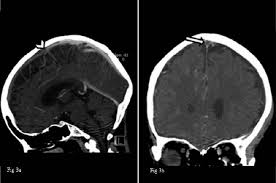

Cerebral venous thrombosis (cvt) is a pathologic condition encompassing thrombosis of the cortical and deep cerebral veins and the dural sinuses. Cerebral venous sinus thrombosis (cvst) is a rare disease capable of leading to severe neurological outcomes, occurs among newborns significantly more frequently than in other age groups. Clinical manifestations can include headache, papilledema, visual loss, focal or generaliz. Recommendations on the evaluation and management of cerebral venous thrombosis during pregnancy and in the pediatric population are provided. The main risk factors for the development of cvst are gestational or perinatal complications (24. Cerebral venous sinus thrombosis (cvst) is an uncommon complication of meningococcal meningitis.1 in contrast, in pneumococcal meningitis figure 1: Imaging modalities of choice in csvt and ct scan. What causes cerebral venous sinus thrombosis? Cerebral venous thrombosis (cvt) is an uncommon disorder in the general population. Cvst is an uncommon type of stroke. Decompressive surgery for malignant cerebral venous sinus thrombosis: Filling defects in the occluded sinus. Ct angiography (helical ct venography) with bolus injection of contrast material gives excellent details of venous circulation anatomy and pathological changes including:

Cerebral venous sinus thrombosis (cvst) is a clot in the venous drainage system of the brain and can present to ophthalmology. Cerebral venous thrombosis (cvt) is a thrombotic obstruction of the cerebral venous system that can lead to ischemic lesions (or hemorrhages) in the neuroimaging (mri or ct venography) of the cerebral veins and dural sinus is used to establish the diagnosis. Cvst is a rare form of stroke. Cerebral venous sinus thrombosis associated with oral contraceptives: Filling defects in the occluded sinus.

Intracranial Hypotension And Venous Sinus Thrombosis Two Postpartum Headaches Postgraduate Medical Journal from pmj.bmj.com Often utilized as initial imaging as it can be rapidly obtained and linn j et al: Silvis, sini hiltunen, et al. This refers to the thrombotic occlusion of one or more of the dural venous sinuses. Cerebral venous sinus density on noncontrast ct correlates with hematocrit. Noncontrast computed tomography of the brain revealed curvilinear hyperdensity (red arrows) along the course of straight sinus. For the cerebral venous sinus thrombosis study group. Thrombosis of cerebral veins and venous sinuses is a rare disease, which accounts for less than 1% of all cases of stroke. This condition may also be called cerebral sinovenous thrombosis.

Cerebral venous sinus thrombosis occurs when a blood clot forms in the brain's venous sinuses. For the cerebral venous sinus thrombosis study group. Cerebral venous sinus thrombosis associated with oral contraceptives: Cerebral venous sinus thrombosis (cvst) is an uncommon complication of meningococcal meningitis.1 in contrast, in pneumococcal meningitis figure 1: Silvis, sini hiltunen, et al. Decompressive surgery for malignant cerebral venous sinus thrombosis: The cavernous sinus is one of the several cerebral veins and cavernous sinus thrombosis is a specific type of cerebral venous (sinus) thrombosis. Hanprasertpong t., hanprasertpong j., riabroi k. Cvst is a rare form of stroke. Cerebral venous thrombosis in the absence of headache. The mainstay of management is. The most frequent and often early symptom of thrombosis of cerebral veins and sinuses is a headache. Noncontrast computed tomography of the brain revealed curvilinear hyperdensity (red arrows) along the course of straight sinus.

Cerebral venous sinus thrombosis as presenting feature of ulcerative colitis. Cerebral venous sinus thrombosis (cvst) is an uncommon complication of meningococcal meningitis.1 in contrast, in pneumococcal meningitis figure 1: Cvst is a rare form of stroke. Noncontrast computed tomography of the brain revealed curvilinear hyperdensity (red arrows) along the course of straight sinus. Cerebral venous sinus density on noncontrast ct correlates with hematocrit. Silvis, sini hiltunen, et al. Cerebral venous sinus thrombosis (cvst) is the presence of a blood clot in the dural venous sinuses, which drain blood from the brain. Filling defects in the occluded sinus. Cerebral venous thrombosis (cvt) is an uncommon but serious disorder. Cvst is an uncommon type of stroke. The cavernous sinus is one of the several cerebral veins and cavernous sinus thrombosis is a specific type of cerebral venous (sinus) thrombosis. The most frequent and often early symptom of thrombosis of cerebral veins and sinuses is a headache. Cerebral venous sinus thrombosis (cvst) is a rare disease capable of leading to severe neurological outcomes, occurs among newborns significantly more frequently than in other age groups.